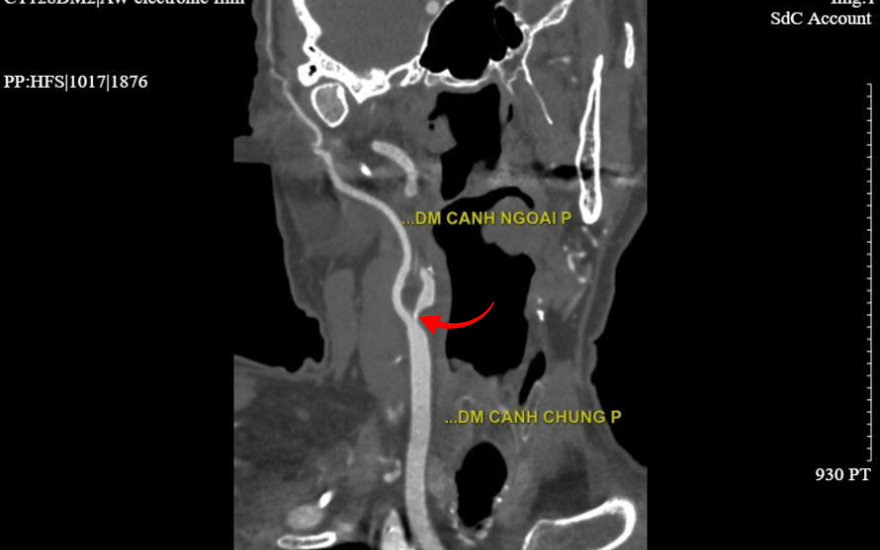

接诊后,红玉 - 福长明综合医院 心血管与介入心脏病科的 高猛兴 (Cao Manh Hung) 硕士、住院医生 立即判断,Halpern 先生的症状符合短暂性脑缺血发作(TIA)的典型表现,提示存在极高的卒中风险。随后进行的相关检查结果显示,患者右侧颈内动脉在开口处即出现极重度狭窄(>90%),并伴有多处动脉粥样硬化斑块。此外,其冠状动脉系统亦发现前降支狭窄超过90%。

2560排CT扫描影像显示的颈动脉狭窄部位

颈动脉狭窄会导致流向大脑的血液减少甚至完全阻断,这正是 Halpern 先生出现上述危险症状的主要原因。高猛兴 (Cao Manh Hung) 医生警告说:“如果血管不能及时得到开通,患者可能面临脑卒中,并留下瘫痪、语言障碍、痴呆等严重后遗症,甚至危及生命。”.